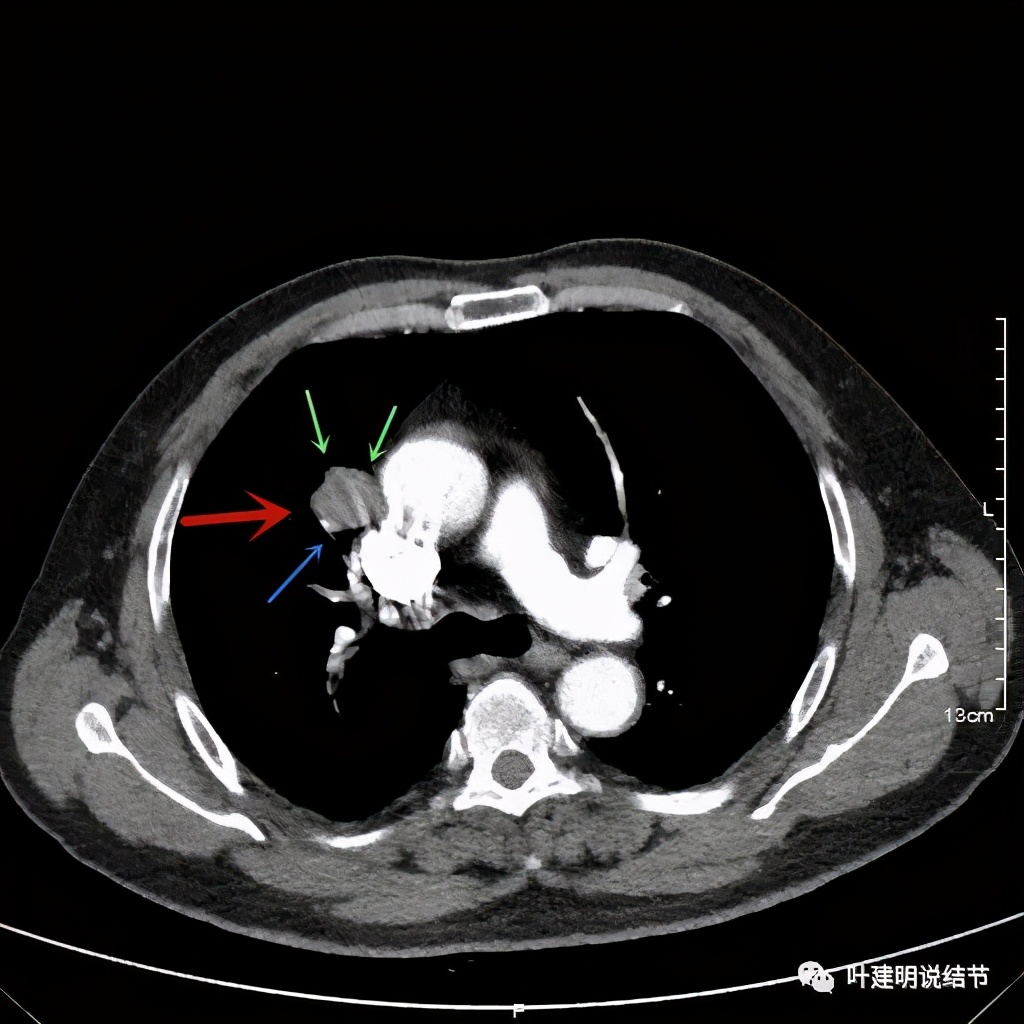

可见右上叶占位,我们现在知道了结果以后回头看,发现病灶的边缘在各个层面都是过于光滑(绿色箭头所示)。血管紧贴病灶边走行(桔色箭头所指),是不是有侵犯看不清楚,若是靶扫描加重建可能会更清楚点。支气管感觉也是贴着病灶走,但有的层面是不是截断,也不看的不太清楚。有的层面见局部有点状高密度(蓝色箭头所指),是不是错构瘤的局部钙化呢?若是纵隔窗又是如何?

上图示病灶

上图示病灶局部点状高密度(蓝色);边缘过于光滑(绿色)

上图示病灶密度不均,但边缘过于光滑(绿色);支气管似有截断(粉色);局部有点状钙化(蓝色)